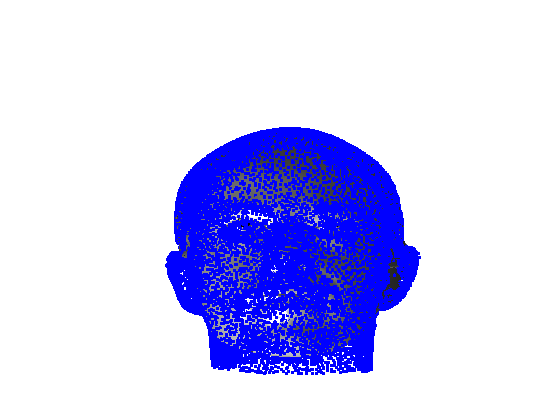

Toolsets to define normal appearance and therefore both assist with planning of surgery and define optimal outcomes from a range of surgical interventions are currently either crude or lacking. Therefore, the unit collected a large, high quality 3D image dataset of 1523 human heads. An example is given in Fig. 1 showing the 3D channel only on the left, and the 3D data with texture pasted on on the right. The data was collected over well-conserved demographics, and an age range of 1 to 89 years, see Fig. 2. The dataset was collected with the aim of developing a normal equivalent of the human cranium and face in order develop the tools to enhance patient experience following surgery. We plan to make the dataset publicly available in the near future.

Our system can accept 3D images in arbitrary pose and employs an automatic landmarking scheme to normalise the pose of the 3D head before any further processing. Two examples of typically varying initial pose taken from the headspace datset are shown in Fig. 4.

Fig. 9 shows examples of the fitted model (trained on FRGC data) on the first four subjects in our Headspace training set. Note that the mean of the landmarks in the sparse model is centred on the orgin, and so the scan data is moved towards that and becomes frontal in pose. We note that other researchers [28] have used 3D landmark localisation to find the head, but often this only includes landmarks that are relatively easy to localise, namely inner eye corners and nose. Localising more landmarks over a wider facial area has a number of advantage in terms of cropping, pose normalisation and global 3D template warping, all of which are described later.